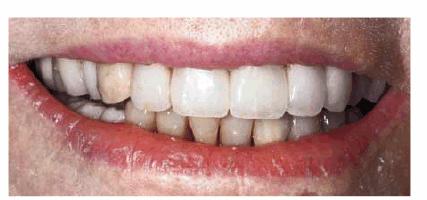

Figure 29-4A shows a 74-year-old woman who was dissatisfied

with her smile but was not sure if she wanted considerable changes made. Her

chief concern was that she did not like her malpositioned lower incisors.

Orthodontics was not an option owing to the cost and length of treatment time.

Cosmetic contouring of the mandibular teeth was selected as a compromise

treatment because of its conservative approach (Figure 29-4B). The patient liked the changes in the lower

teeth and subsequently asked about options for improving the maxillary teeth.

Finances remained an issue, so cosmetic bonding was selected as the treatment

plan of choice. Figures 29-4C, and 29-4D show the patient's maxillary teeth before and after

cosmetic bonding.

Figure 29-4A: This 74-year-old woman was dissatisfied with the appearance of her teeth.

Figure 29-4B: Cosmetic contouring was done to make the mandibular teeth appear straighter; the maxillary incisors were direct bonded with composite resin.

Figure 29-4C: Although a compromise to full restorative esthetics, just treating a limited amount of anterior teeth can satisfy the older patient.

Figure 29-4D: At 90 years of age, this patient is still motivated to improve her smile-now with porcelain laminates. Although the treatment is still a compromise because of her inability to sit through many long appointments, she is slowly involving more teeth in the restorative process.